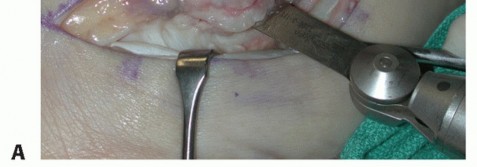

| We use a standard lateral incision along the course of the peroneal tendons, taking care not to injure the sural nerve. | |||

| Carry the incision down to the level of the peroneal tendon sheath (TECH FIG 1A). | |||

TECH FIG 1 • A. Intraoperative photograph of a left ankle (lateral approach) shows the peroneal tendons subluxing anteriorly (brevis is the gray arrowhead , longus is the white arrowhead , SPR is the black arrow). B. The peroneal tendons have been retracted anteriorly by the Penrose drain. Elevation of an anterior-based periosteal flap (outlined by dots) from the fibular groove has been completed. The black arrow shows the remnant of the SPR posteriorly. C. The tendons are relocated, after a groove-deepening procedure, into the recreated groove. The white dots outline the anteriorly based periosteal flap. It is then brought over to the posterior remnant of the SPR (black arrow). D. The flap is sutured to the remnant SPR with nonabsorbable sutures, completing the superior peroneal retinaculoplasty. |

TECH FIG 1 • A. Intraoperative photograph of a left ankle (lateral approach) shows the peroneal tendons subluxing anteriorly (brevis is the gray arrowhead , longus is the white arrowhead , SPR is the black arrow). B. The peroneal tendons have been retracted anteriorly by the Penrose drain. Elevation of an anterior-based periosteal flap (outlined by dots) from the fibular groove has been completed. The black arrow shows the remnant of the SPR posteriorly. C. The tendons are relocated, after a groove-deepening procedure, into the recreated groove. The white dots outline the anteriorly based periosteal flap. It is then brought over to the posterior remnant of the SPR (black arrow). D. The flap is sutured to the remnant SPR with nonabsorbable sutures, completing the superior peroneal retinaculoplasty.